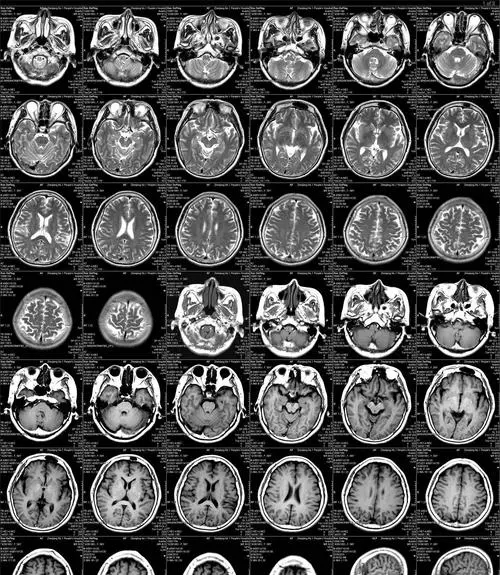

人們生病的時(shí)候,去醫(yī)院看病,有的時(shí)候需要做常規(guī)檢查,例如,ct 彩超,B超之類的,這些疾病都是要通過醫(yī)院片子來展現(xiàn),醫(yī)用激光膠片在對(duì)于現(xiàn)代醫(yī)院的臨床診斷中,有很重要的作用,對(duì)于醫(yī)用膠片的知識(shí),我們需要多多的注意,隨著社會(huì)的發(fā)展,醫(yī)用膠片的清晰度也是越來越高的,很多人在對(duì)于醫(yī)用膠片的問題也有很多,對(duì)于醫(yī)用膠片的問題,本次醫(yī)用膠片廠家康迪告訴您關(guān)于醫(yī)用激光膠片的知識(shí)

隨著醫(yī)學(xué)科學(xué)技術(shù)的發(fā)展,醫(yī)用膠片的種類不斷豐富,許多基于傳統(tǒng)黑白彩色膠片的新型醫(yī)用激光膠片逐漸進(jìn)入人們的視野。由于各種優(yōu)勢(shì),受到各大醫(yī)院的追捧和青睞。

醫(yī)用激光膠片采用連續(xù)色調(diào)輸出技術(shù),使圖像的動(dòng)態(tài)范圍、清晰度、對(duì)比度、灰度更加直觀、生動(dòng)、準(zhǔn)確。生成的圖像空間分辨率可達(dá)650像素/英寸,輸出灰度可達(dá)14位,優(yōu)于市面上的紙張和PET膠片。